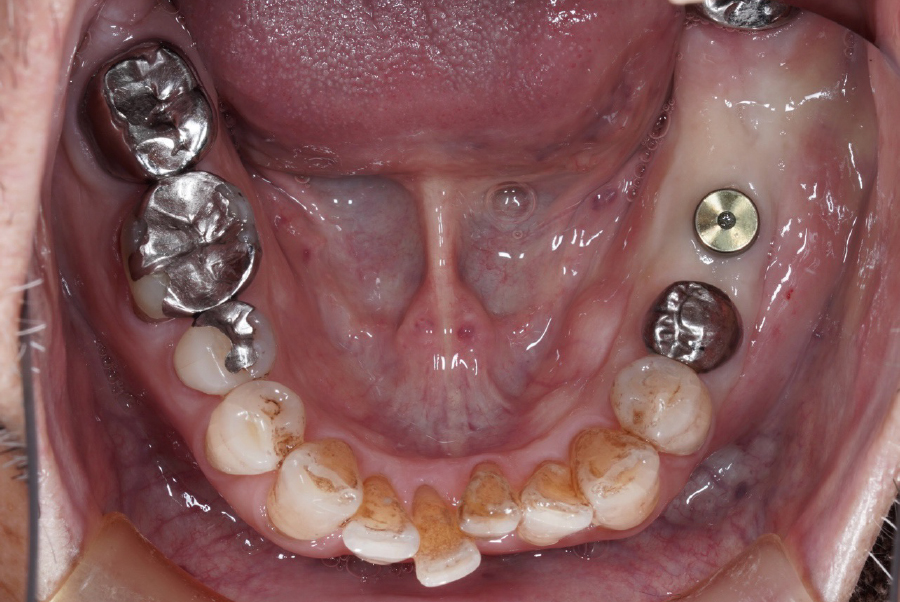

治療中の様子

治療にあたっては、CTによる精密診断を行い、骨量・骨質・神経の位置関係を詳細に評価しました。その結果、左下6番部位において十分な初期固定が得られる条件が整っていたため、インプラント1本で機能回復を図る治療計画としています。

インプラントを1本にすることで、外科的侵襲を最小限に抑えつつ、周囲の歯に負担をかけない形で咀嚼機能の回復が可能となりました。

抜歯後、左下6番にインプラントを1本埋入し、周囲の歯に負担をかけない形で機能回復を行いました。